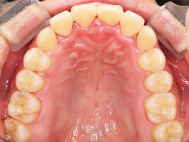

Before

| 症状 | 上顎前歯部叢生 |

上の前歯がハの字隣の歯が引っ込んでいる

前歯のガタガタが気になるとの事で来院されました。

装着が目立ちたくないとの事でアライナ-での矯正を希望されました、歯の間を削り少し歯の幅をスリムにして綺麗なアーチに並びました。